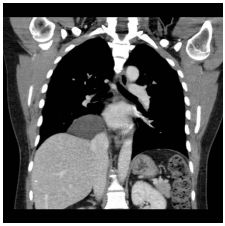

3. This 72-year-old diabetic man was taken to ER for productive cough for 10 days, and rapid progressive dyspnea for 2 days. He also had fever and chill for a week.